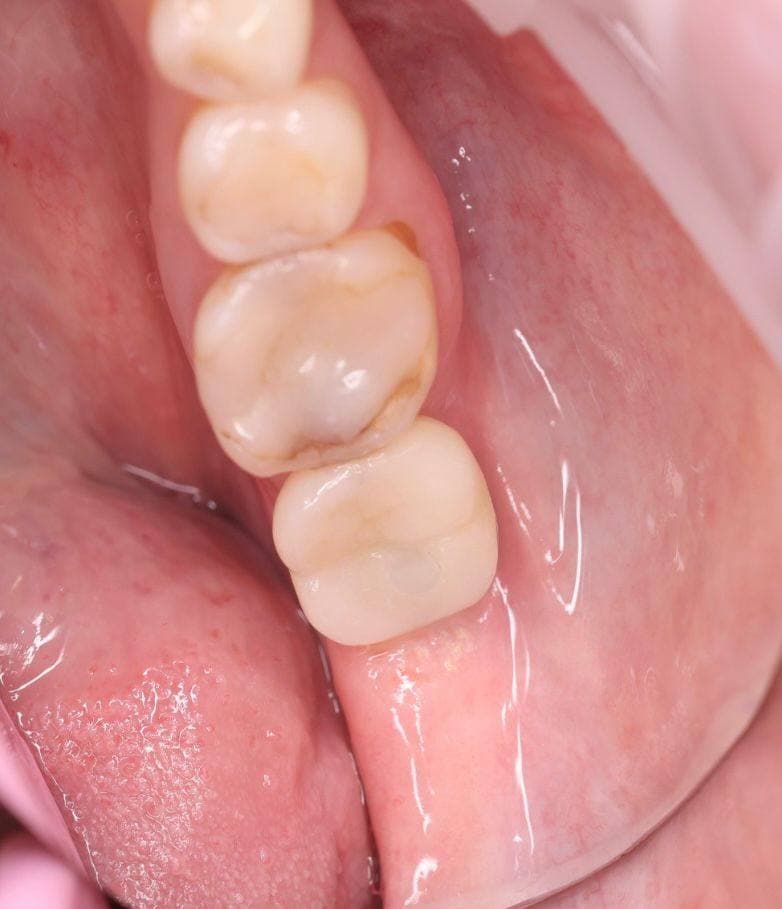

Восстановление бокового зуба (штифтом), разрушенного более чем на 1/2